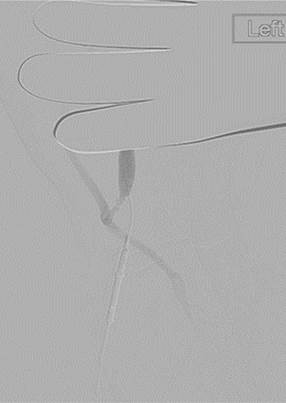

Trombectomía de oclusión de fístula braquiocefálica izquierda

Fistulograma que demuestra la oclusión trombótica de una fístula AV braquiocefálica izquierda (nota: reflujo arterial de contraste).

Tras la primera pasada con el catéter DVX de AngioJet (no se usaron trombolíticos).